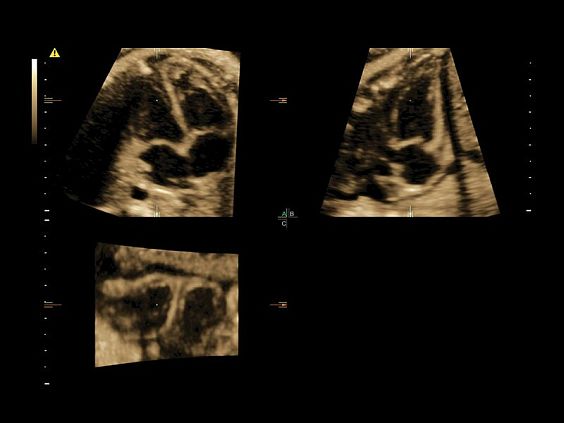

• Томографический ультразвук (TUI)

• Объемное контрастирование прямой плоскости - Basic VCI (VCI-A + VCI static)

• Advanced VCI (Volume Contrast Imaging) - расширенный программный пакет объемного контрастного изображения (VCI) для механических и электронных объемных датчиков:

• Проведение любой произвольной плоскости в 3D/4D (OmniView)

• Объемное контрастирование любой произвольной плоскости (OmniView+VCI)

• Усовершенствованный режим объемной визуализации с контрастированием (Volume Contrast Imaging, VCI) и опция OmniView

• Повышает контрастное разрешение и улучшает визуализацию области интереса в любой плоскости сечения, даже при исследовании структур неправильной формы.